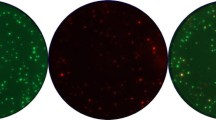

Overall results from sixteen IFNγ-ELISPOT protocols using serum-supplemented and serum-free media. a Recovery of viable PBMC using trypan blue and a manual haemocytometer, following resting for 2–20 h. b Background spot production (spots per 100,000 PBMC) in the cells plus medium only control. c Detection rates, shown as % of responses detected among the seven possible donor–antigen combinations. The mean values for all samples (D1–D5) and all labs (n = 16) were used to plot minimum and maximum value, the range (error bars), inter-quartile range (boxes), median (horizontal line) and mean (black triangle) for the whole group under serum supplemented or serum-free conditions

Viable cells were counted immediately after thawing and again after the mandatory resting phase in the assay. Twelve centers performed manual counting using a microscope and trypan blue exclusion. Three centers used Guava-readers and one used a CASY cell counter, while also providing complementary data sets for manual counting. The mean number of viable cells based on trypan blue exclusion (for all 5 donors) immediately after thawing was 10.6 ± 3.3 × 106 per vial, with a minimum of 4.3 and a maximum of 18.1 × 106 cells being reported by the participants. After resting, the mean number of viable cells was decreased compared to direct counting following thawing, with an average cell loss of approximately 31–40% (Table 1). However, there was no significant difference between the results obtained in the presence of serum (mean 7.3 × 106 cells) compared to resting in the absence of serum (mean 6.4 × 106 cells) (Table 1; Fig. 1a). We concluded that the number of viable cells was not compromised in serum-free medium.

Background spot production under serum-supplemented and serum-free conditions

We then compared the induction of non-specific background spots under serum and serum-free conditions. For this, background spot frequency was calculated for each center for each of the five donors (D1–D5) under both conditions. As background spot production in the wells containing cells plus medium only was similar in quantity and distribution among the group of 16 laboratories for all 5 donors (not shown), the average values for all 5 donors, with serum and without serum, were then compared directly (Fig. 1b). The mean background spot values with and without serum were not significantly different (4.9 and 4.7 per 100,000 PBMC, respectively), suggesting that the presence of serum in the medium does not affect background spot production. The median background spot production, which is less affected by the three outliers with high background was 1.1 (serum) and 1.8 (serum-free) spots per 100,000. The background values observed for the majority of laboratories was below two spots per 100,000 PBMC.

Detection rates in serum-supplemented and serum-free conditions

The detection of influenza- and/or CMV-specific reactivities was subject to the strict acceptance criteria that we had previously defined ([10]; “Materials and methods”). Laboratory performance was expressed as the detection rate, calculated as the percentage of all potential responses that were detected (Fig. 1c). In the whole group of centers, detection rates were not significantly different for serum and serum-free conditions (P = 0.33, Student’s t test). Under test conditions with serum, 63.7% of all responses were detected for the whole group, with seven laboratories reporting >85% detection rates. Under serum-free conditions, 52.9% of the responses were detected for the whole group, and 4 laboratories reported >85% detection rates. Comparison of the performance of individual laboratories revealed that nine centers reported approximately equal detection rates (<15% difference) under both conditions, two centers generated better results and five centers encountered decreased detection rates using serum-free medium (>15% difference; Supplementary Table 2A). Importantly, the majority (13/16) of laboratories had optimized their protocols for use with serum and not for serum-free conditions. These laboratories combined serum with one of the following media: RPMI (6×), IMDM (4×), X-Vivo 15 (2×) and Iscove (1×). The three laboratories that normally used serum-free protocols added serum to X-Vivo 15 (2×) or RPMI (1×). The analysis of these small data sets did not reveal differences in the detection of positive responses in relation to the type of medium used.

We have used a multicenter approach to study the impact of serum use in a broad variety of ELISPOT protocols by comparing the performance of 16 different laboratories. Numbers of viable cells after thawing and resting were similar for both conditions (Fig. 1a), demonstrating that cell quality was not compromised in serum-free media. Similarly, there was little difference between the levels of background spot production under serum and serum-free conditions (Fig. 1b), suggesting that serum is not a major factor contributing to background spot detection. Overall detection rates (expressed as the percentage of detected among potentially detectable responses) did not differ significantly between the two conditions (Fig. 1c). The fact that four laboratories were able to detect >85% responses without serum clearly illustrates that excellent results can be obtained with serum-free protocols. However, five laboratories (38%) found that the detection rates decreased when they switched from using their serum-containing test medium to a serum-free medium. It has to be emphasized that 13/16 of the laboratories in this panel employ ELISPOT protocols that had been optimized for the use of serum supplemented medium. Based on these findings we recommend the use of serum-free protocols to centers that perform ELISPOT assays for monitoring immune responses on a regular basis, as this should eliminate the problems associated with batch-testing and serum stability, and assist in the process of assay harmonization. Our observations are in line with those from a recent, single center study [11], which concluded that removal of serum and addition of low-dose IL-7 led to increased test performance when applied to a specific ELISPOT protocol. During the review process of our paper an additional inter-laboratory study was published by Zhang et al. [14], where the use of eight different sera was compared to the use of the same serum-free medium in a single optimized protocol. The results showed that signal to noise ratio increased in the presence of serum, and confirmed that good performance can be achieved using an optimized serum-free protocol. In contrast, our study of a variety of different locally established protocols clearly shows that removal of serum can increase the performance in some laboratories, while decreasing performance in others (i.e., increased background spot production or lower numbers of antigen-specific spots), and that ELISPOT assays can be successfully performed under completely different but for each laboratory optimized conditions. We conclude that not all protocols support high performance under serum-free conditions without re-optimization.